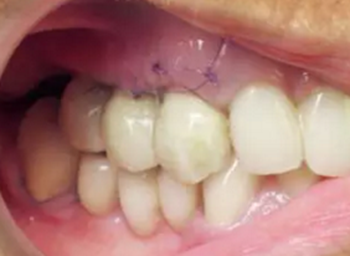

患者65歲,女性,非吸煙者,全身狀況欠佳,希望重獲咀嚼能力?;颊呶盖谐蟪霈F(xiàn)惡病質(zhì),消化功能受損,從而導(dǎo)致口腔狀況加重(圖1)。

圖1

患者3區(qū)磨牙缺失,#26冠修復(fù),頜曲線已改變。#13~15松動(dòng)3度(Lindhe和Muehlmanm分度)。牙根齲壞并根折,#14、15牙齦炎癥明顯但沒(méi)有膿腫和上頜竇炎。#47伸長(zhǎng),#47~43固定橋頜曲線異常。并沒(méi)有足夠的頜間距離能夠使#16作為拮抗。